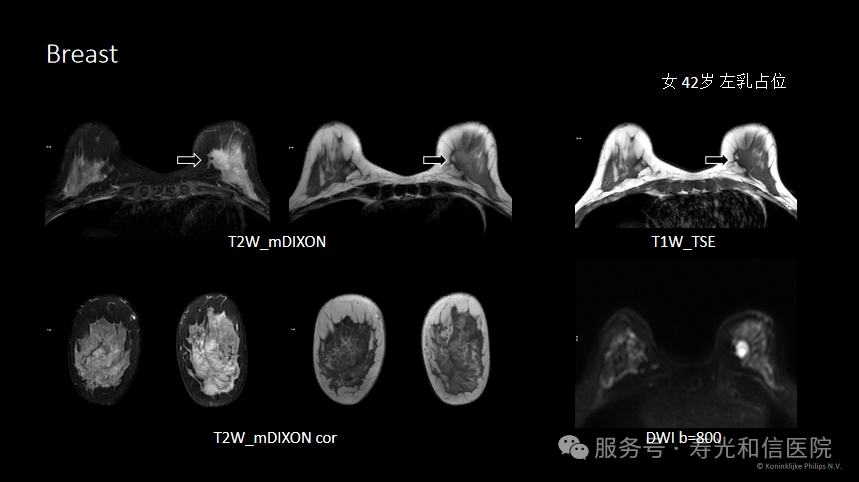

1. 穿透致密乳腺:亚洲女性中,约60%的乳腺属于“致密型”(腺体多、脂肪少),钼靶和超声可能漏掉藏在腺体中的肿瘤,而MRI可以“透视”致密组织,发现微小病灶。

2. 发现早期癌变:MRI对肿瘤的血液供应非常敏感,能捕捉到毫米级的早期癌变或高危病变(如导管原位癌)。

3. 评估肿瘤范围:对于已确诊乳腺癌的患者,MRI能清晰显示肿瘤的实际大小、是否侵犯周围组织,帮助医生制定精准的手术方案。